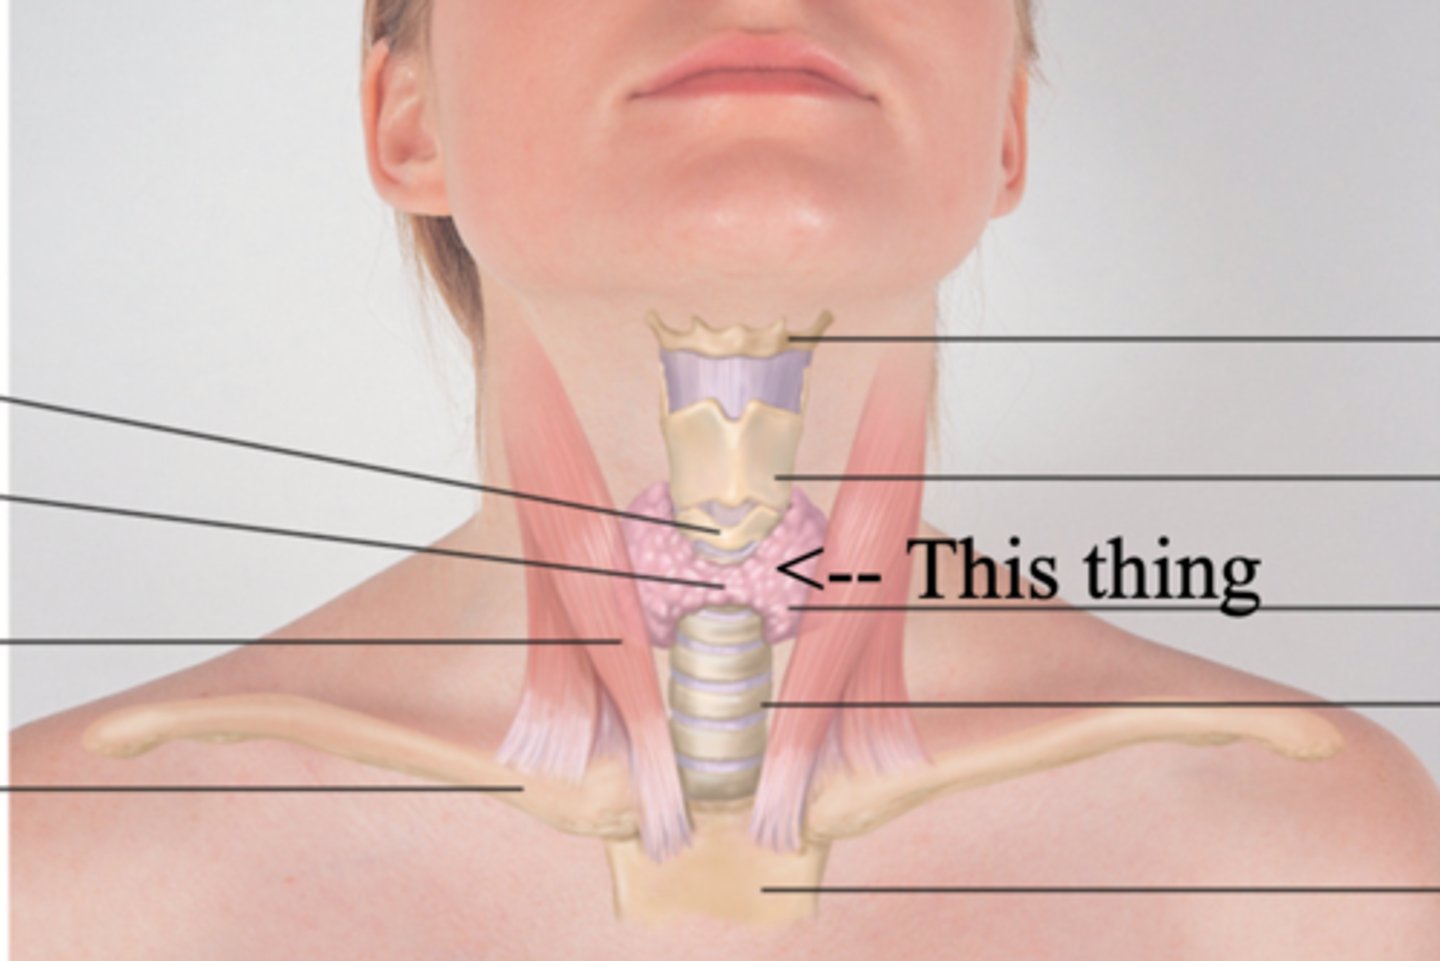

Thyroid Gland

A gland found in the neck that secretes calcitonin, T3, and T4 hormones

T3 and T4 Hormones

Hormones that stimulates rate of cellular metabolism

Calcitonin

Hormone that lowers blood calcium levels

Objective Data to Assess for Neck

- Thyroid gland (advanced skill; can auscultate for bruit)

Bruit

Blowing, swooshing sound heard through a stethoscope over an area of abnormal blood flow